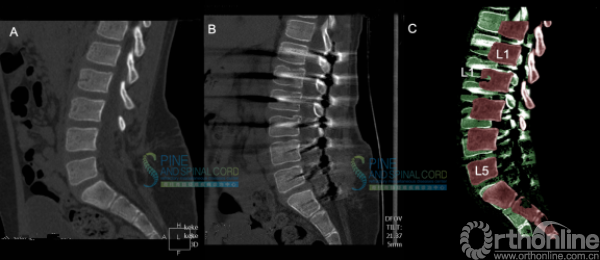

病例四 脊髓栓系综合征伴脊髓纵裂

患者女,34岁,因左下肢疼痛2年,加重1年入院;

2年前无明显诱因出现双下肢疼痛,近1年疼痛加重,不能久坐。无排便排尿困难,无鞍区感觉障碍;

体检:四肢肌力5级,双下肢腱反射亢进,病理征未引出。